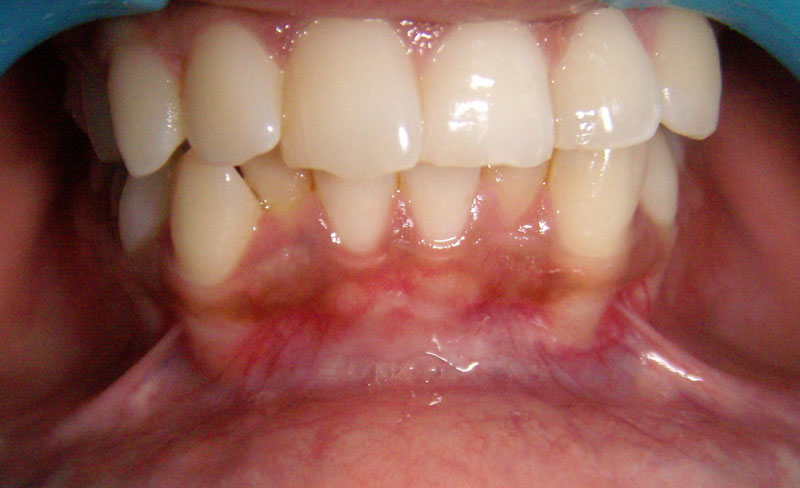

Before

After